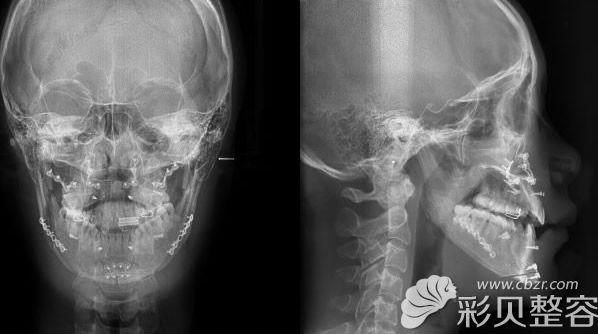

我难看的下巴并不是天生的,而是4岁时不小心摔伤后及时治疗造成的。下巴脸骨严 重变形,还有骨性反颌。拍了X光片后,才知道突出的下巴竟然有17mm。这也是我发音不准和咬合不齐的元凶。

从x光照片和术前照片中看得出来,我上下颚畸形和厉害。多位医生会诊后,制定了手术方案:

1、朴相薰医生,使用T字截骨术和下颌角整形,通过【无捆绑双颚手术】和【V-Line下颌角手术】来矫正地包天和咬合不正的情况;